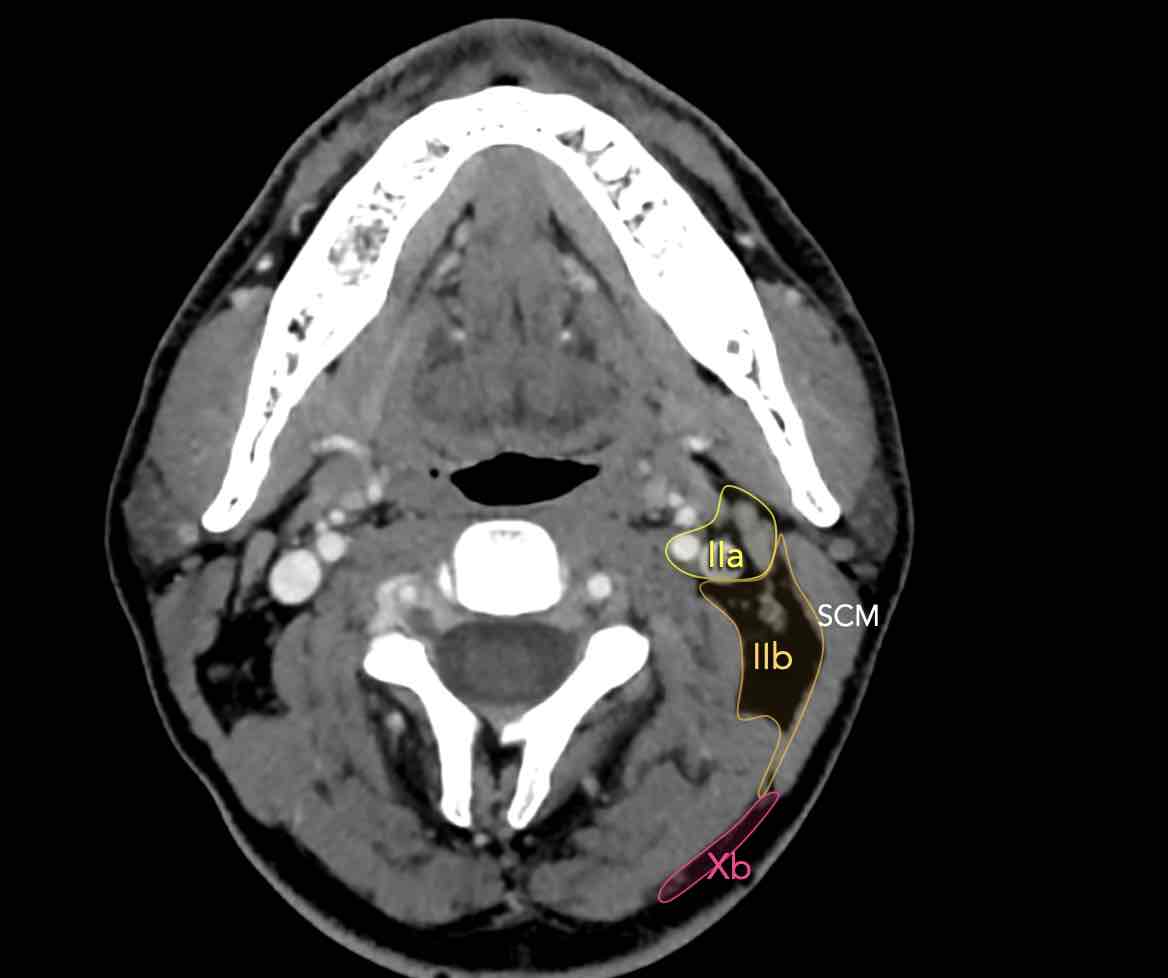

II – Tĩnh mạch cảnh trên

Tầng II nhận bạch huyết hướng tâm từ mặt, tuyến mang tai, và các hạch dưới hàm, dưới cằm và sau hầu.

Tầng II cũng nhận trực tiếp các bạch mạch thu thập từ hốc mũi, hầu, thanh quản, ống tai ngoài, tai giữa, và các tuyến dưới lưỡi và dưới hàm [1].

Tầng II có thể được chia thành tầng IIa và tầng IIb bằng cách vẽ một đường tại bờ sau của tĩnh mạch cảnh trong.

Các hạch bạch huyết ở tầng IIa và IIb có nguy cơ chứa di căn từ các ung thư hốc mũi và khoang miệng, vòm hầu, hầu miệng, hạ hầu, thanh quản và các tuyến nước bọt lớn.

Tầng IIb thường liên quan hơn đến các khối u nguyên phát ở hầu miệng hoặc vòm hầu, và ít thường xuyên hơn với các khối u ở khoang miệng, thanh quản hoặc hạ hầu [1].